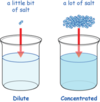

Drugs are usually weak acid/bases and not readily

lipid soluable

Drugs can become ionized when dissolved in water depending on

The pH of solution and property of molecule.

The pKa is the solution a drug becomes

50/50 ionized/non-ionized in

acid need alkaline environments and vice versa